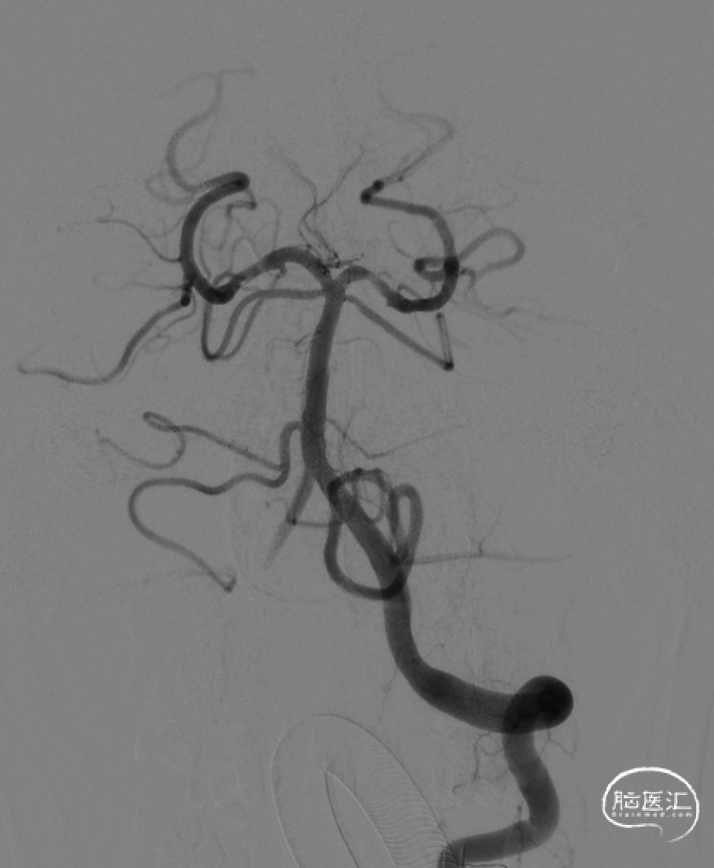

急诊脑血管造影:基底动脉顶端、左侧大脑后动脉血管闭塞。

患者造影显示基底动脉顶端、左侧大脑后动脉血管闭塞,急性发病,发病后很快意识昏迷,左侧瞳孔散大,造影结果和临床表现符合,考虑血栓负荷量较大;有急诊取栓指征。

术后使用BCG造影显示3级再通。